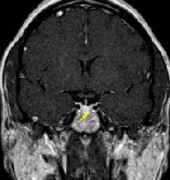

• 術(shù)中磁共振(iMRI)在復(fù)發(fā)性垂體瘤神經(jīng)內(nèi)鏡手術(shù)中的作用

術(shù)中磁共振(iMRI)在復(fù)發(fā)性垂體瘤神經(jīng)內(nèi)鏡手術(shù)中的作用

2020-02-28 12:25:43

垂體瘤 作為顱內(nèi)較常見的腫瘤之一,其發(fā)生率僅次于腦膠質(zhì)瘤和腦膜瘤,約占顱內(nèi)腫瘤的8%-15% 。盡管垂體瘤大多數(shù)為良性腫瘤,但部分患者術(shù)后已消失的...